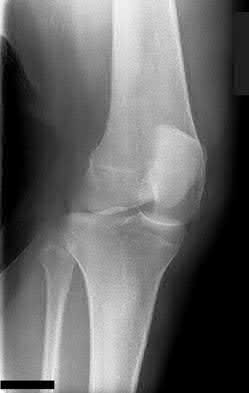

1. # A 32-year-old male sustains the injury shown in Figure A and undergoes treatment as shown in Figure B. Following placement of this implant, what is the best technique to confirm it is not too proud proximally?

1. Lateral radiograph of the knee

2. AP radiograph of the knee

3. Oblique radiographs of the knee

4. Merchant radiograph of the knee

5. Internally rotated 45 degree view of the knee Corrent answer: 1

The safe zone for tibial nail placement as seen on radiographs is just medial to the lateral tibial spine on the anteroposterior radiograph and immediately adjacent and anterior to the articular surface as visualized on the lateral radiograph.

Tornetta et al specifically located the safe zone for nail entry in a study using fresh frozen cadaver knees. The authors found that the safe zone for nail placement is located 9.1+/-5 millimeters lateral to the midline of the plateau and three millimeters lateral to the center of the tibial tubercle. The width of the safe zone averaged 22.9 millimeters and was as narrow as 12.6 millimeters.

The starting point of the of the nail can be best viewed on the lateral knee radiograph, an example of which is shown in Illustration A. Illustration B shows the "sweet spot" for nail insertion as defined by Tornetta.